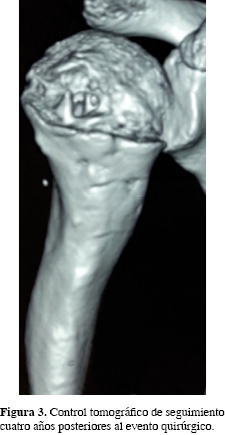

El objetivo de este trabajo es presentar los resultados del tratamiento de una paciente con QOA en húmero proximal, con resección quirúrgica de la lesión con técnica de eggshell más aplicación de injerto no vascularizado de peroné y su evolución satisfactoria a cuatro años.

Se trata de una paciente del género femenino de 7 años de edad, sin antecedentes de importancia para el padecimiento actual, quien sufre una caída desde su plano de sustentación e ingresa por contusión directa en hombro derecho, dolor, aumento de volumen en húmero proximal y limitación funcional. Fue manejada con analgésicos no esteroideos sin mejoría. La radiografía simple mostró lesiones líticas y trabeculares en húmero proximal derecho (Figura 1), la tomografía axial simple, una imagen osteolítica con patrón quístico difuso en metáfisis proximal de húmero por debajo de la fisis (Figura 2) y el gammagrama óseo con aumento de la captación compatible con proceso tumoral en húmero proximal sin metástasis. La fosfatasa alcalina fue de 290 UI/l (normal 44 a 147 UI/l), deshidrogenasa láctica de 65 UI/l (normal 60 a 70 UI/l), calcio sérico de 10 ng/dl (normal 8.9 a 10.1 mg/dl); resto de estudios dentro de parámetros normales. El resultado histopatológico reportó quiste óseo aneurismático. Fue manejado con legrado y resección intralesional con técnica eggshell, colocación de injerto óseo autólogo de peroné izquierdo libre no vascularizado y estabilización con clavo centromedular de Steinman el cual se retiró a las 12 semanas posteriores. A los cuatro años la paciente, está asintomática, sin evidencia de recidiva de la lesión por tomografía axial computarizada (Figura 3) y con regeneración total del sitio de toma del injerto peroneo (Figura 4).